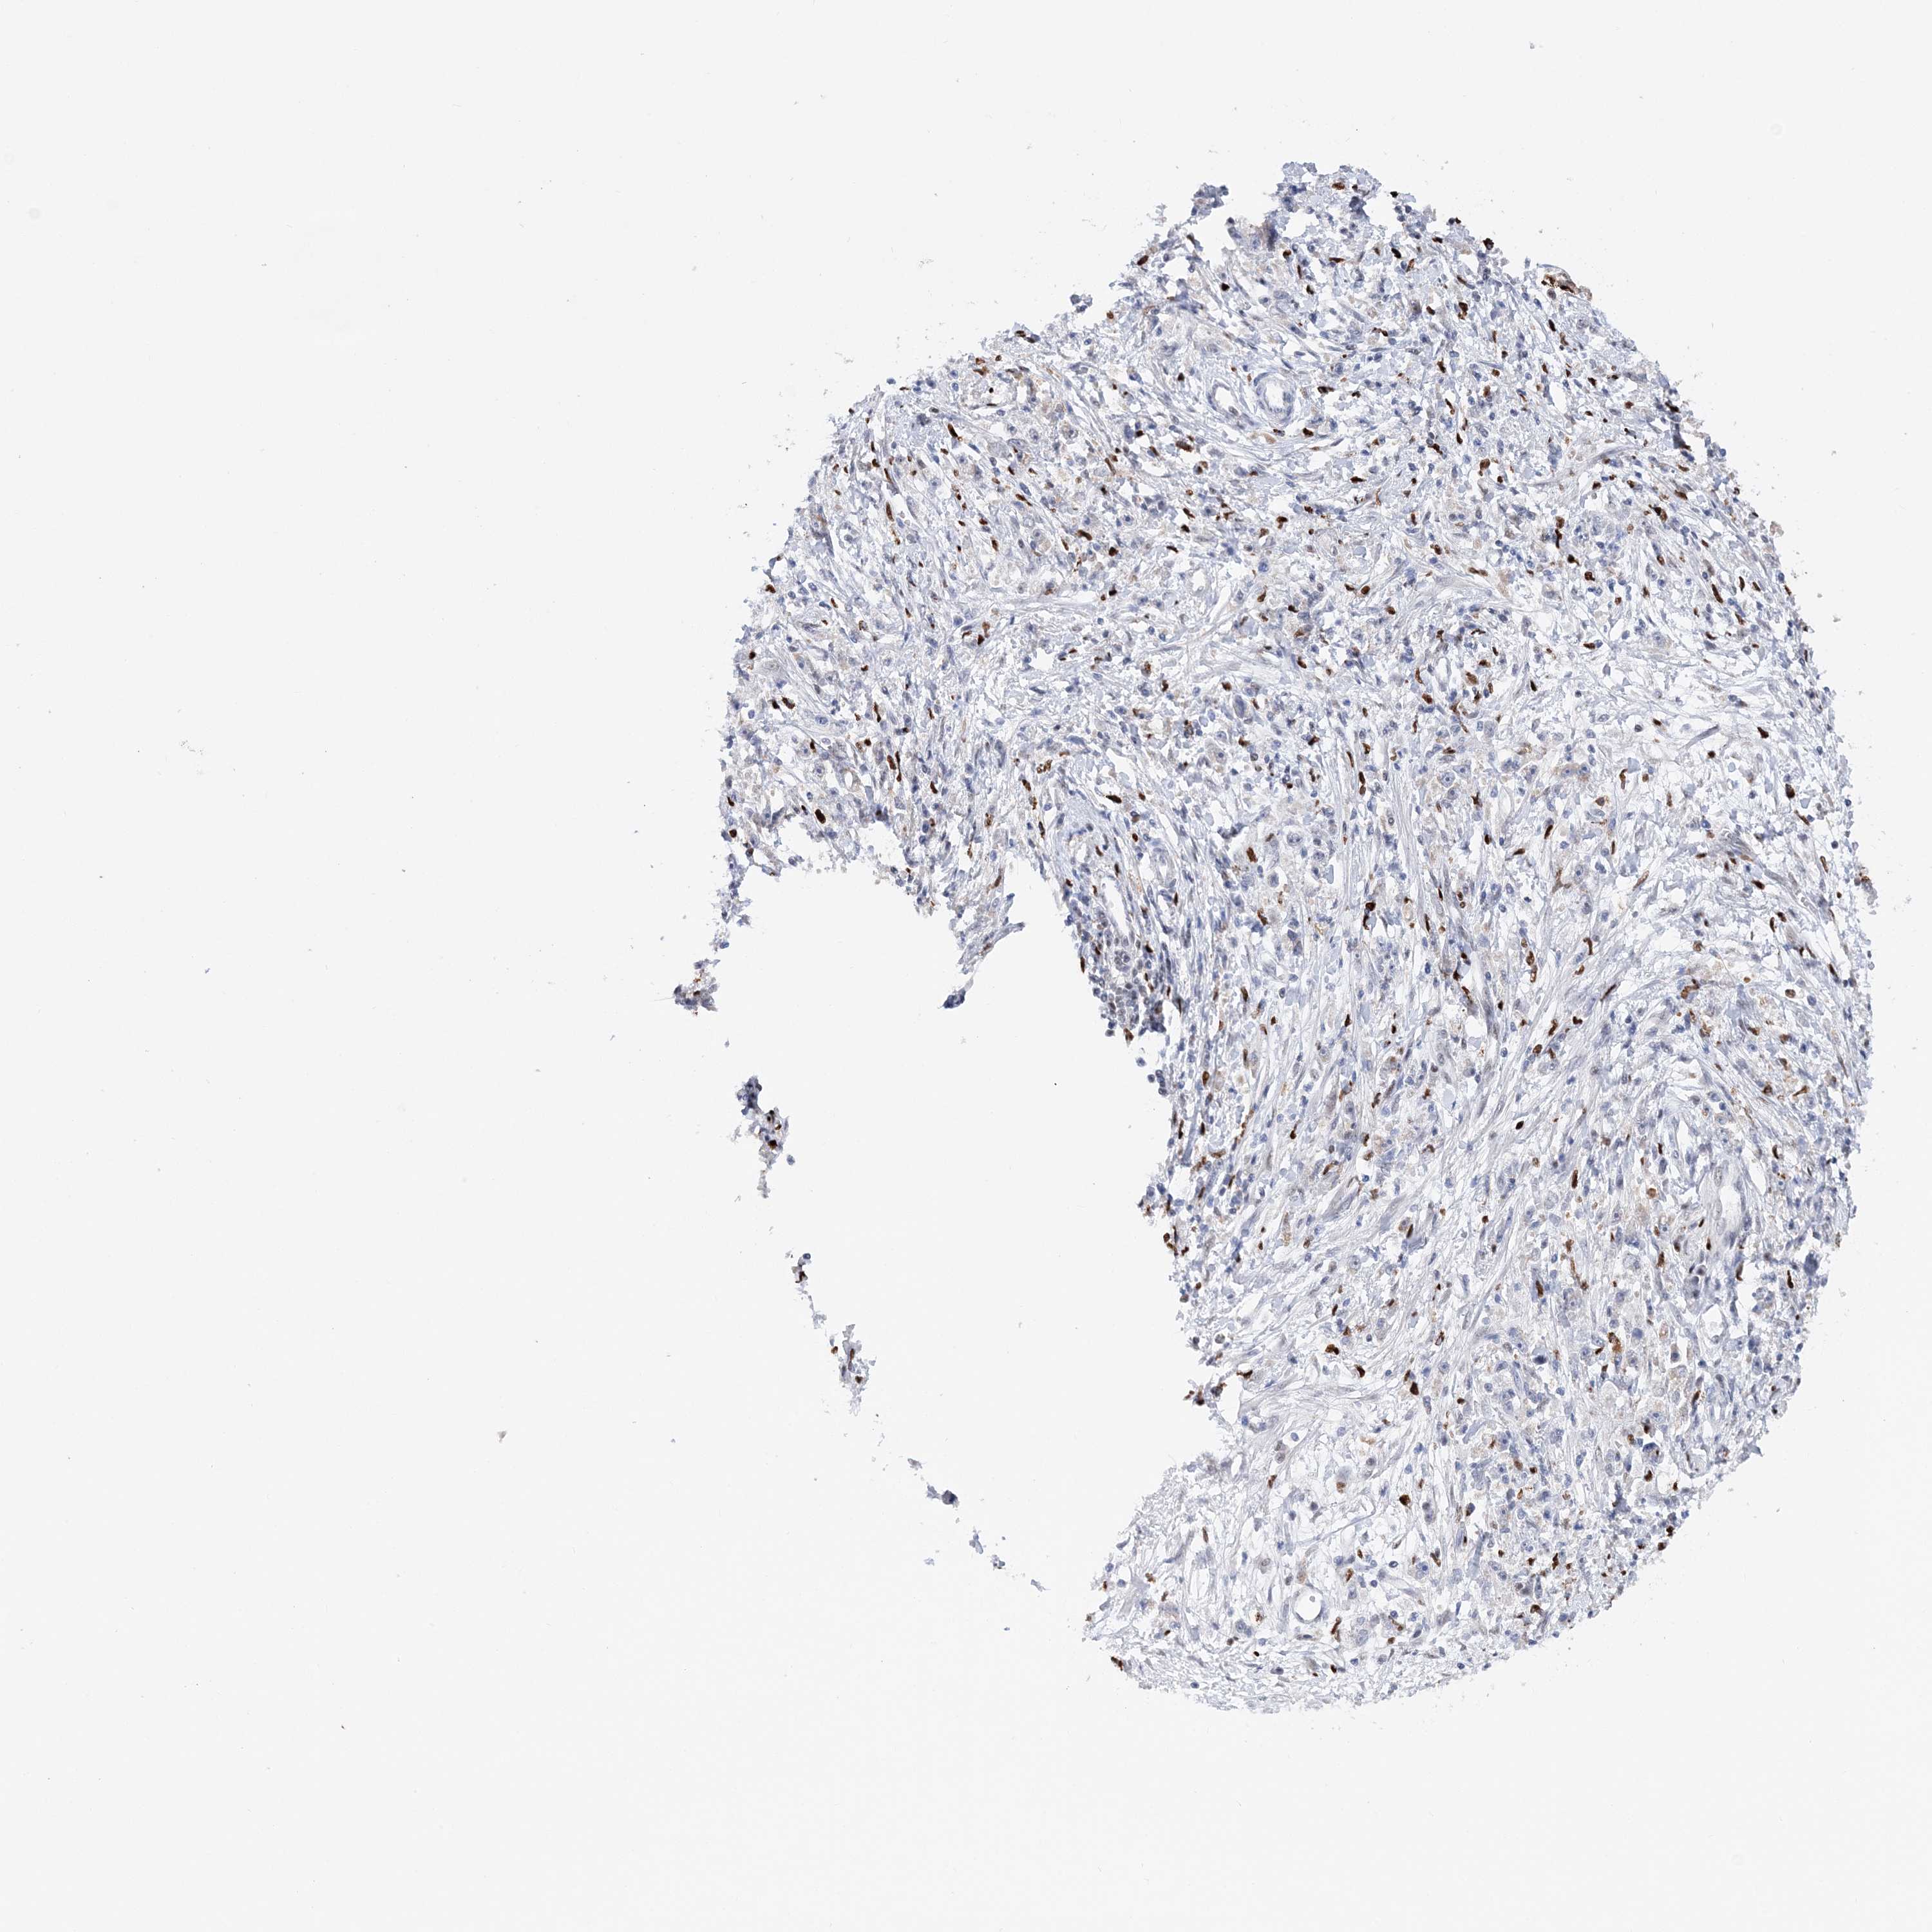

STOMACH CANCER - Protein expressioni

A mouse-over function shows sample information and annotation data. Click on an image to view it in a full screen mode. Samples can be filtered based on level of antibody staining by selecting one or several of the following categories: high, medium, low and not detected. The assay and annotation is described here.

Note that samples used for immunohistochemistry by the Human Protein Atlas do not correspond to samples in the TCGA dataset.

Antibody stainingi

Antibody staining in the annotated cell types in the current human tissue is reported as not detected, low, medium, or high, based on conventional immunohistochemistry profiling in selected tissues. This score is based on the combination of the staining intensity and fraction of stained cells.

Each image is clickable and will lead to virtual microscopy that enables deeper exploration of all samples and also displays staining intensity scores, fraction scores and subcellular localization as well as patient and tissue information for each sample.

Antibody HPA036999

Antibody HPA041289

Staining

High

Medium

Low

Not detected

Intensity

Strong

Moderate

Weak

Negative

Quantity

>75%

75%-25%

<25%

None

Location

Nuclear

Cytoplasmic/membranous

Cytoplasmic/membranous,nuclear

Adenocarcinoma, NOS

Adenocarcinoma, High grade